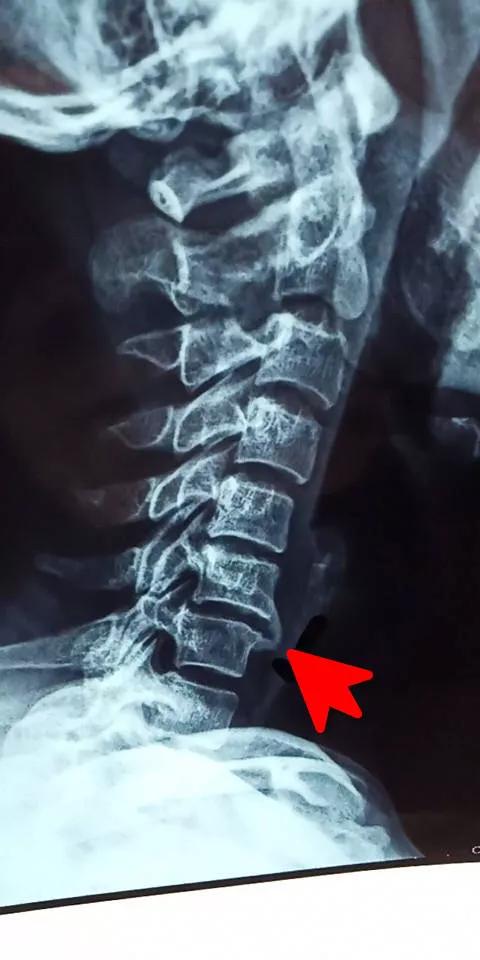

5、椎间盘椎体滑脱。

颈椎椎体滑脱